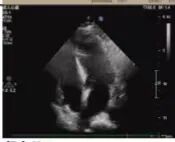

2025年深秋的一個(gè)清晨,82歲的馬奶奶(化名)因持續(xù)胸悶氣短被家人送至醫(yī)院心內(nèi)科。心臟超聲檢查顯示,她的左心房?jī)?nèi)有一個(gè)直徑近5厘米的腫瘤,隨心跳規(guī)律擺動(dòng),如同一個(gè)隨時(shí)可能破裂的“不定時(shí)炸彈”。更危急的是,冠脈造影進(jìn)一步揭示其冠狀動(dòng)脈多支血管嚴(yán)重狹窄,左前降支狹窄達(dá)95%,回旋支中段完全閉塞,右冠狀動(dòng)脈彌漫性病變—兩種致命性心臟疾病的疊加,讓這位高齡患者的生命岌岌可危。

術(shù)前超聲